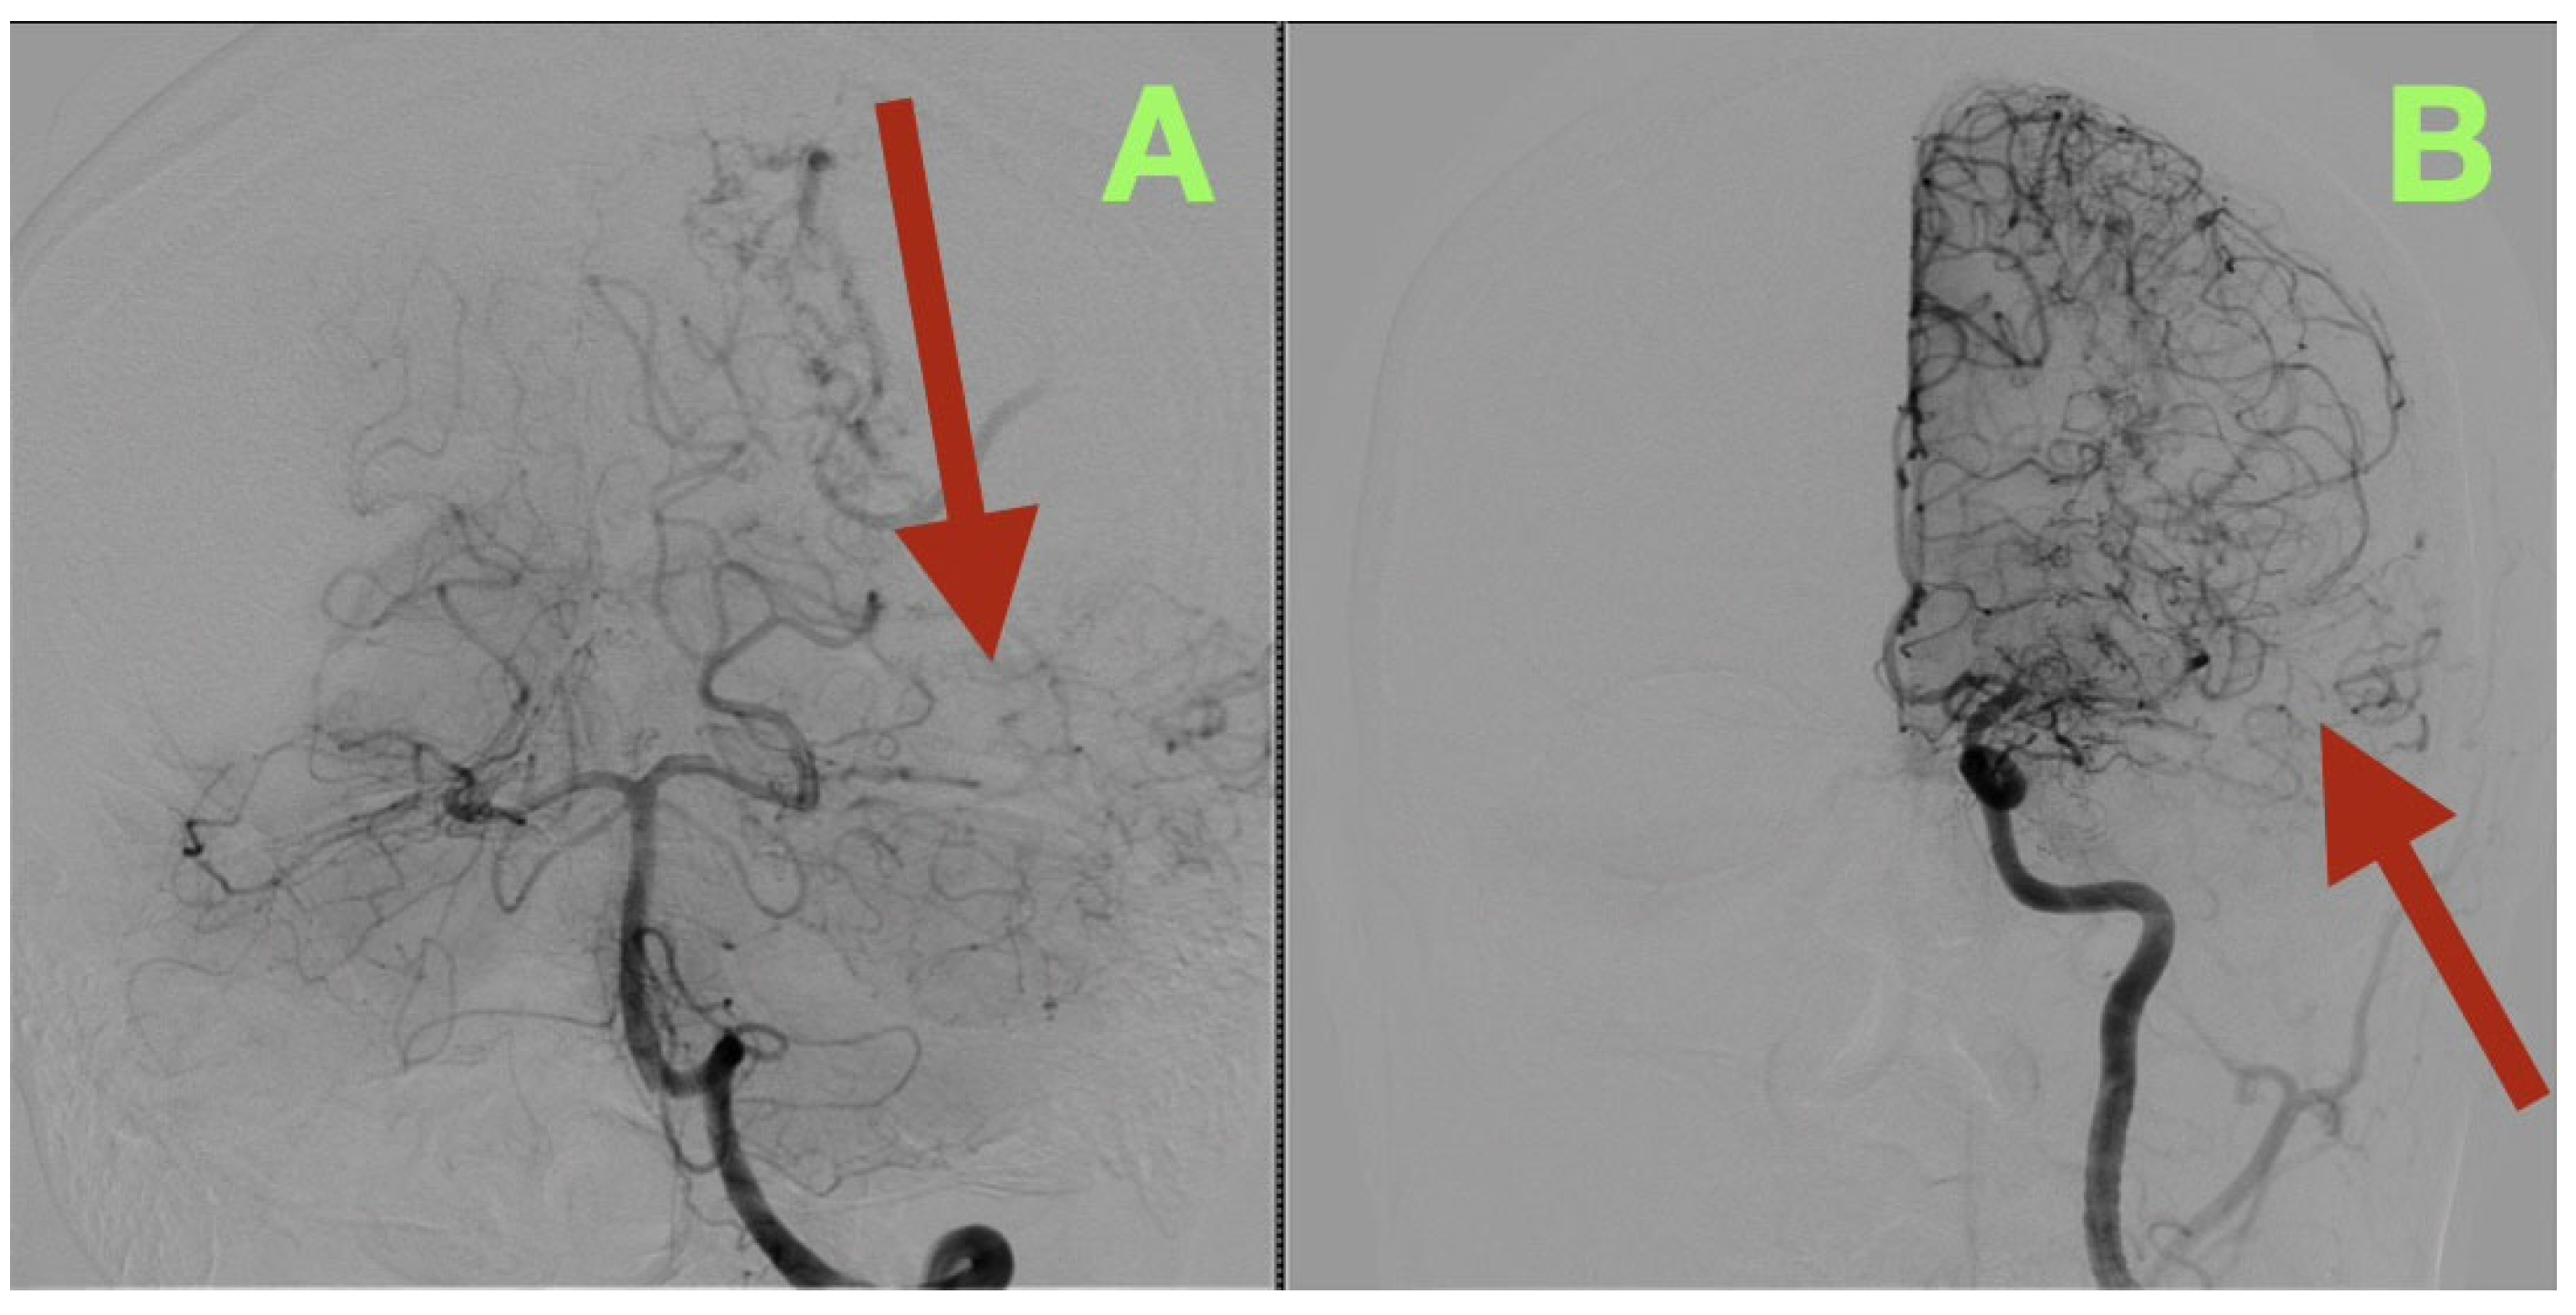

Angiographic studies, particularly selective cerebral angiography, utilizing bilateral internal carotid and left vertebral artery injections established a comprehensive, detailed vascular map of the suspected lesion clinically determined to be an AVM. Selective cerebral angiography established the presence of a compact, high-flow left temporo-parieto-occipital AVM of approximate dimensions 40 × 30 mm in size. The AVM nidus was located deep to the confluence of the posterior superior temporal, angular, and lateral occipital gyri, which is an anatomically unique location representing the crossroads of the posterior perisylvian cortex, visual association areas, and posterior inferior parietal lobule (Figure 1A–D).

Location of the nidus of this AVM also placed it in close proximity to several critical white matter tracts: Meyer’s Loop, the arcuate fasciculus, the inferior fronto-occipital fasciculus, and the inferior longitudinal fasciculus. Each of these structures courses through the same narrow white matter corridor in millimeters of each other.

Three-dimensional rotational angiography provided further details about the relationship between the nidus and the surrounding cortex. The nidus is densely packed with tortuous vessels that form a tangential interface with eloquent cortical regions (Figure 2A,B). The short pial feeder enters at nearly perpendicular angles and the venous outflow exits tangentially along the cortical surface. The configuration of the feeder and outflow results in the least amount of transparenchymal penetration possible, however the result of such is maximal cortical hemodynamic exposure. The hemodynamic pattern corresponds directly to the patient’s neurologic deficits: the feeders from the posterior temporal and angular cortices caused the patient’s expressive aphasia secondary to arcuate fasciculus disruption; the occipital extension caused the patient’s contralateral visual field loss; and the periventricular venous congestion caused the patient’s mild right sided pyramidal dysfunction.

Figure 2. Three-dimensional rotational angiography reconstructions. (A): Left lateral oblique view showing the compact nidus (arrow) embedded beneath the posterior superior temporal and angular gyri. The close spatial relationship to the arcuate fasciculus and Meyer’s loop explains the patient’s expressive aphasia and right inferior quadrantanopia. (B): Posterior oblique projection illustrating the deep extension of the nidus toward the occipital surface (arrow) and the tangential entry of short pial feeders from M4 and P4 branches. The surrounding venous system demonstrates smooth, ectatic channels draining into both the superior sagittal and transverse-sigmoid sinuses, confirming a mixed superficial-deep outflow pattern.